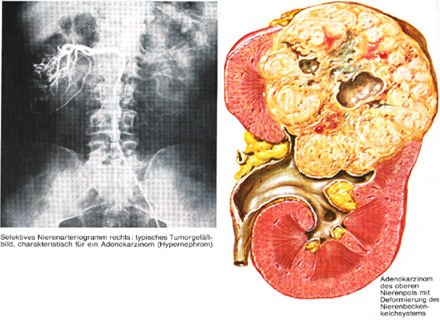

Böbrek adenokanseri; Renal Cell (hücreli) Ca (kanser), Hipernefrom veya Grawitz tümörü gibi isimlerle de anılır. Bütün malign tümörlerin %3’ünü, böbrekteki malign tümörlerinin de %86’sını oluşturur.

Patolojisinde; yuvarlak-oval, kirli sarı renkte yer yer hemorajik, nekrotik, kistik ve kalsifik alanları yer yer yumuşak ve sert alanlar içeren pseudokapsüllü bir tümördür.

Başlangıçta intrarenal olan tümör ekspansif (çevre dokuya doğru genişleyerek) olarak gelişir, tümör çevresindeki böbrek dokusunu iterek böbrek konturunu (dış yapısını) bozar. Aynı şekilde kaliksleri ve pelvisi iterek pelvikalisiyel deformasyona (bozulmaya) neden olur. Zamanla böbrek fibroz kapsülünü geçerek perirenal yağ dokuya, Gerota fasyasına, çevre doku ve organlara ulaşır, böbrek fikse (sabit, hareket etmeyen) kitle halini alır.

Ürografi (DÜSG-İVP): Böbrek konturlarında büyüme, düzensizlik ya da bombeleşme, psoas gölgesinde silikleşme, pelvikalisiel deformasyon, alt kutup tümörlerinde üreterin mediale itilmesi, parankim harabiyeti sonucu fonksiyon kaybı izlenir.

Renal Angiografi: Solid tümörlerin ayırıcı tanısında CT’nin yetersiz kaldığı olgularda damarları kasacak bir madde ve boya verilip içi boyandığında; tümörlü alanlarda oluşan yeni damarlarda kasılma (kontraksiyon) olmamasıyla ayırt edici tanı yapılır.